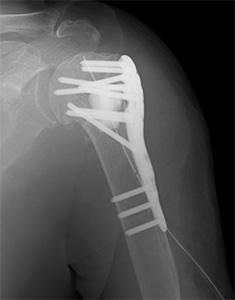

上腕骨近位部骨折(肩の骨折)

高齢者の転倒時に肩や腕を強打して生じることが多い骨折です。

高齢化に伴い、発生数が増加しています。

必要に応じて地域の他病院と連携しながら、もとの日常生活への復帰を目指します。

• 画像:骨折観血的手術(上腕)プレート固定

骨折観血的手術(上腕)

プレート固定